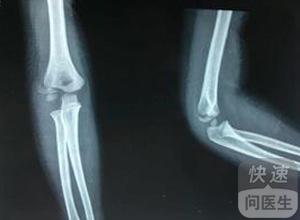

出现了肱骨骨折的情况就需要及时的进行治疗,目前治疗这个疾病最为常见的方法就是手术疗法,进行手术治疗一定要考虑保持关节的活动度,手术之后要注意复位和固定。一般身体情况良好的患者在手术之后当天就可以起床,之后可以...